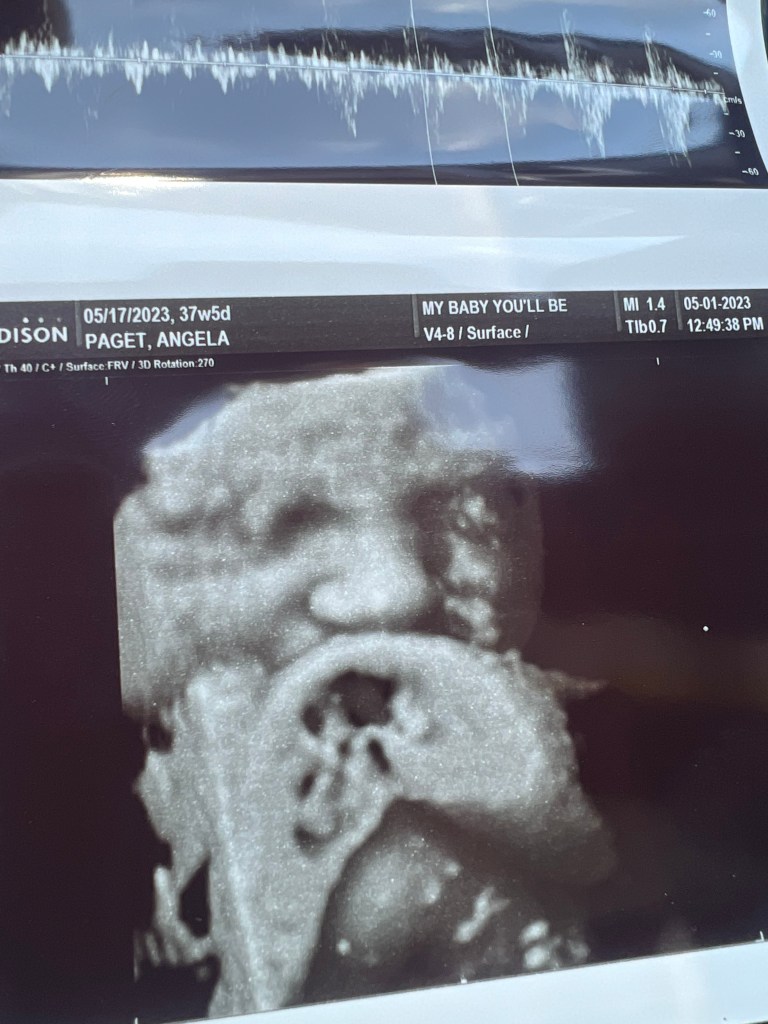

At my 38 week appointment Last week I did an ultrasound with My Baby You’ll Be and it brought such peace of mind. I don’t have any ultrasounds after 26 weeks because my OB typically doesn’t offer more than 2 (26 weeks/6 weeks). I do like that they are non-invasive with pregnancies but I also get a little curious as to how baby is doing and looking and all the things. I was already 37 weeks along so the recommended time frame for a 4D picture had expired out. However, they were able to get a little snap of his face showing just above his nose. He looks so cute and I am so excited to meet him even more. From the looks of it, he looks to have a Jackson nose just like Benny. Hmmm… so curious as to what other features he will have. Bennett was a total surprise because I expected a ginger with blue eyes and light skin. He is all the opposite of those things! He came out olive, full head of dark hair and beautiful dark eyes. We were able to see that Declan has hair too! Again, so curious as to the coloring of his skin, his eyes and his hair.